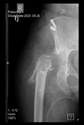

The radiological examination allowed us to verify the close bone-to-implant contact and the unchanged position of the implant during follow-up.

In all the cases operated with the above-described targeting procedure, the stems of the cups remained between the cortical bone surfaces without perforation of the linea terminalis, as shown by postoperative radiographs. There were no complicated surgical situations. In 16 cases, the wound healings were uneventful, and the hips were able to bear weight again after postoperative rehabilitation.